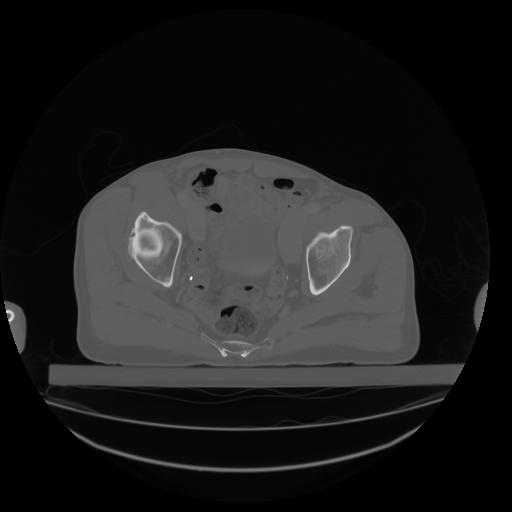

27 CUERPO,CE,Axial,3.0,CUERPO,,